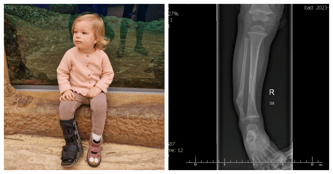

Cel kampanii: Operacja ortopedyczna w Paley European Institute, leczenie i rehabilitacja

Serdecznie dziękujemy za udział w biegu oraz za okazane wsparcie finansowe. Dzięki Państwa zaangażowaniu i hojności udało się zebrać środki, które pozwoliły na zakup sprzętu rehabilitacyjnego dla Antosi.

Wasza pomoc to nie tylko wsparcie materialne, ale również ogromny gest solidarności i nadziei dla Antosi. To dzięki Wam Antosia może iść cały czas do przodu – dosłownie i w przenośni – na własnych nogach.